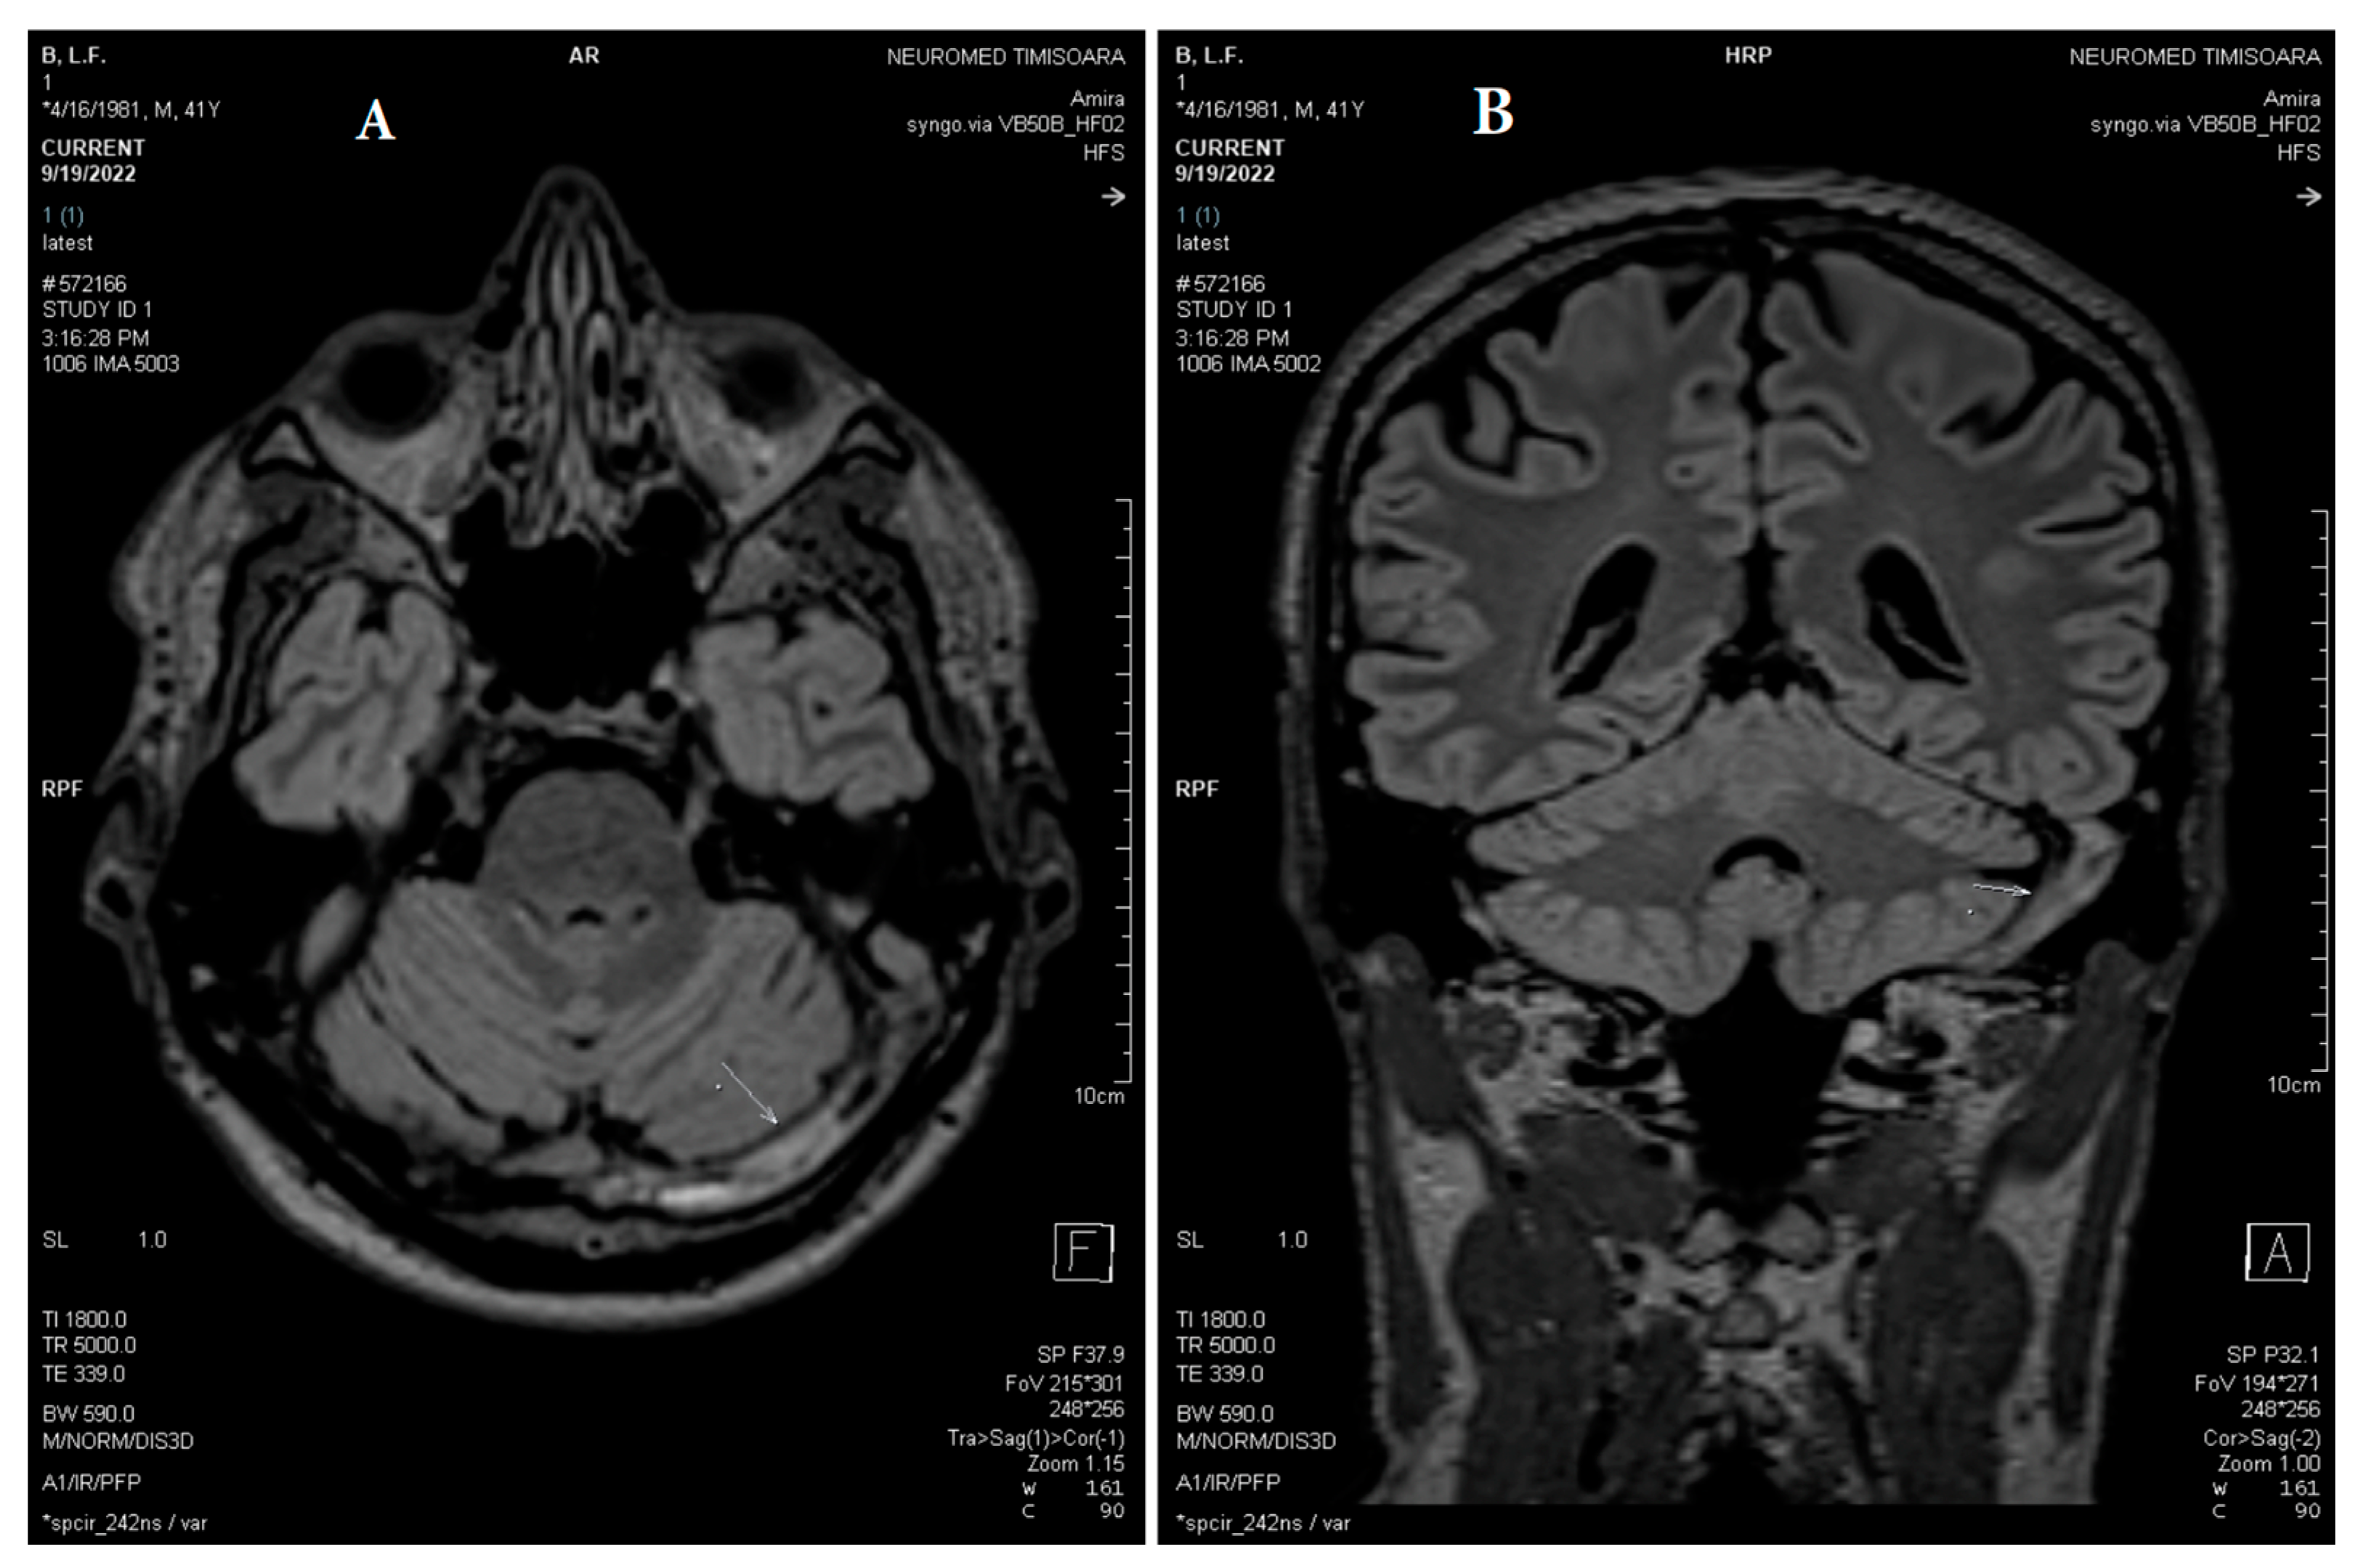

2.2. Neuroimaging Data